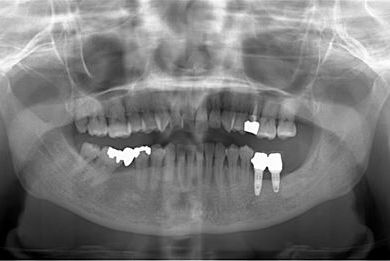

インプラントの症例写真 IMPLANT

インプラント治療

| 性別/年齢 | 女性 / 46歳 | ||||||||||||||||||||||||||||||||

| 主訴 | 左奥歯のインプラント治療を希望。 | ||||||||||||||||||||||||||||||||

| 治療方針 | 左下奥、欠損部分をインプラント治療にて、機能的・審美的回復を行う。 | ||||||||||||||||||||||||||||||||

| 治療内容 | インプラント2本、ハイブリッドセラミッククラウン2本 | ||||||||||||||||||||||||||||||||

| 総治療費 | 399,000円 | ||||||||||||||||||||||||||||||||

| 治療期間 | 5ヶ月 |